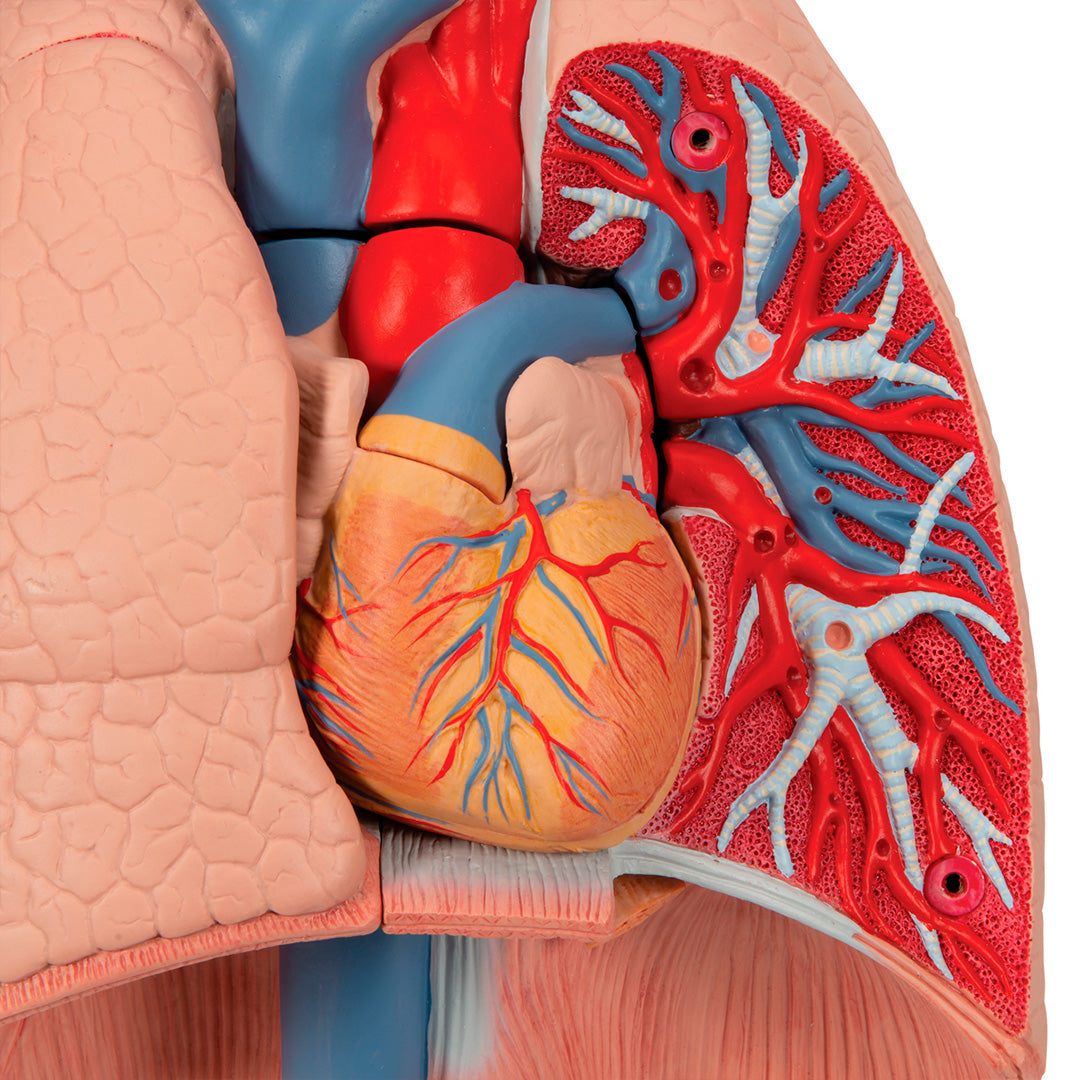

Modelo del pulmón, 7 piezas

Modelo del pulmón, 7 piezas

Descripción

Una sección aumentada y muy detallada a través de la mitad derecha del encéfalo, incluyendo una porción del cráneo.

Tiene dos lados y está coloreado delicadamente.

El modelo incluye 49 referencias, identificables en las indicaciones en inglés.